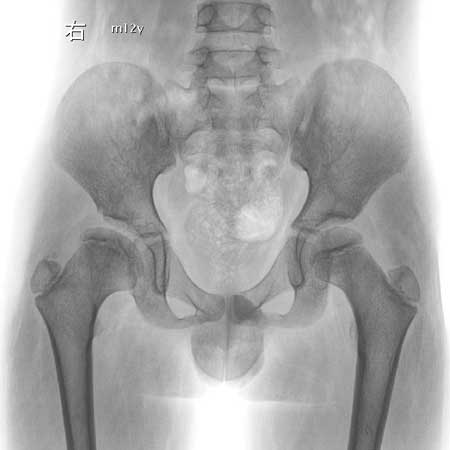

男,12岁,

右侧髋臼发育不良。扁平髋?

右侧髋臼发育不良

右侧先天性髋脱位

1右侧髋臼扁平,浅小

2右侧股骨头形状不规则,呈扁平状

3右股骨头向外上方脱位

4右股骨颈短小

右侧髋臼发育不良。扁平髋。